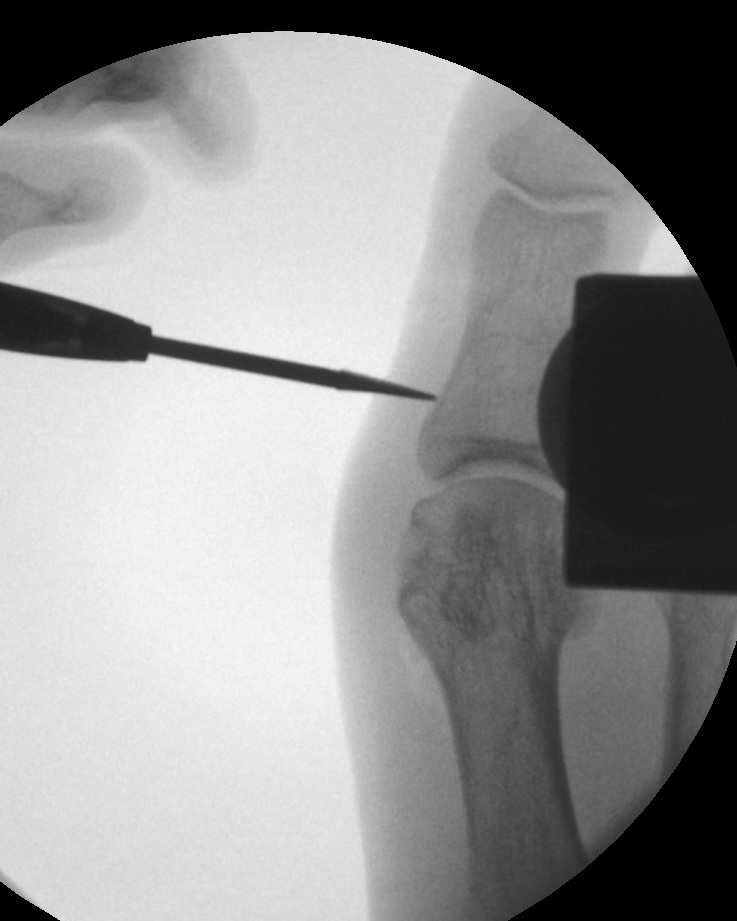

Operationstechnik (Text und Fotos)

Zum Lesen der Bildbeschreibung und zur Vollansicht bitte die Bilder anklicken. Bilder: Dr. med. Gerhard Kaufmann.